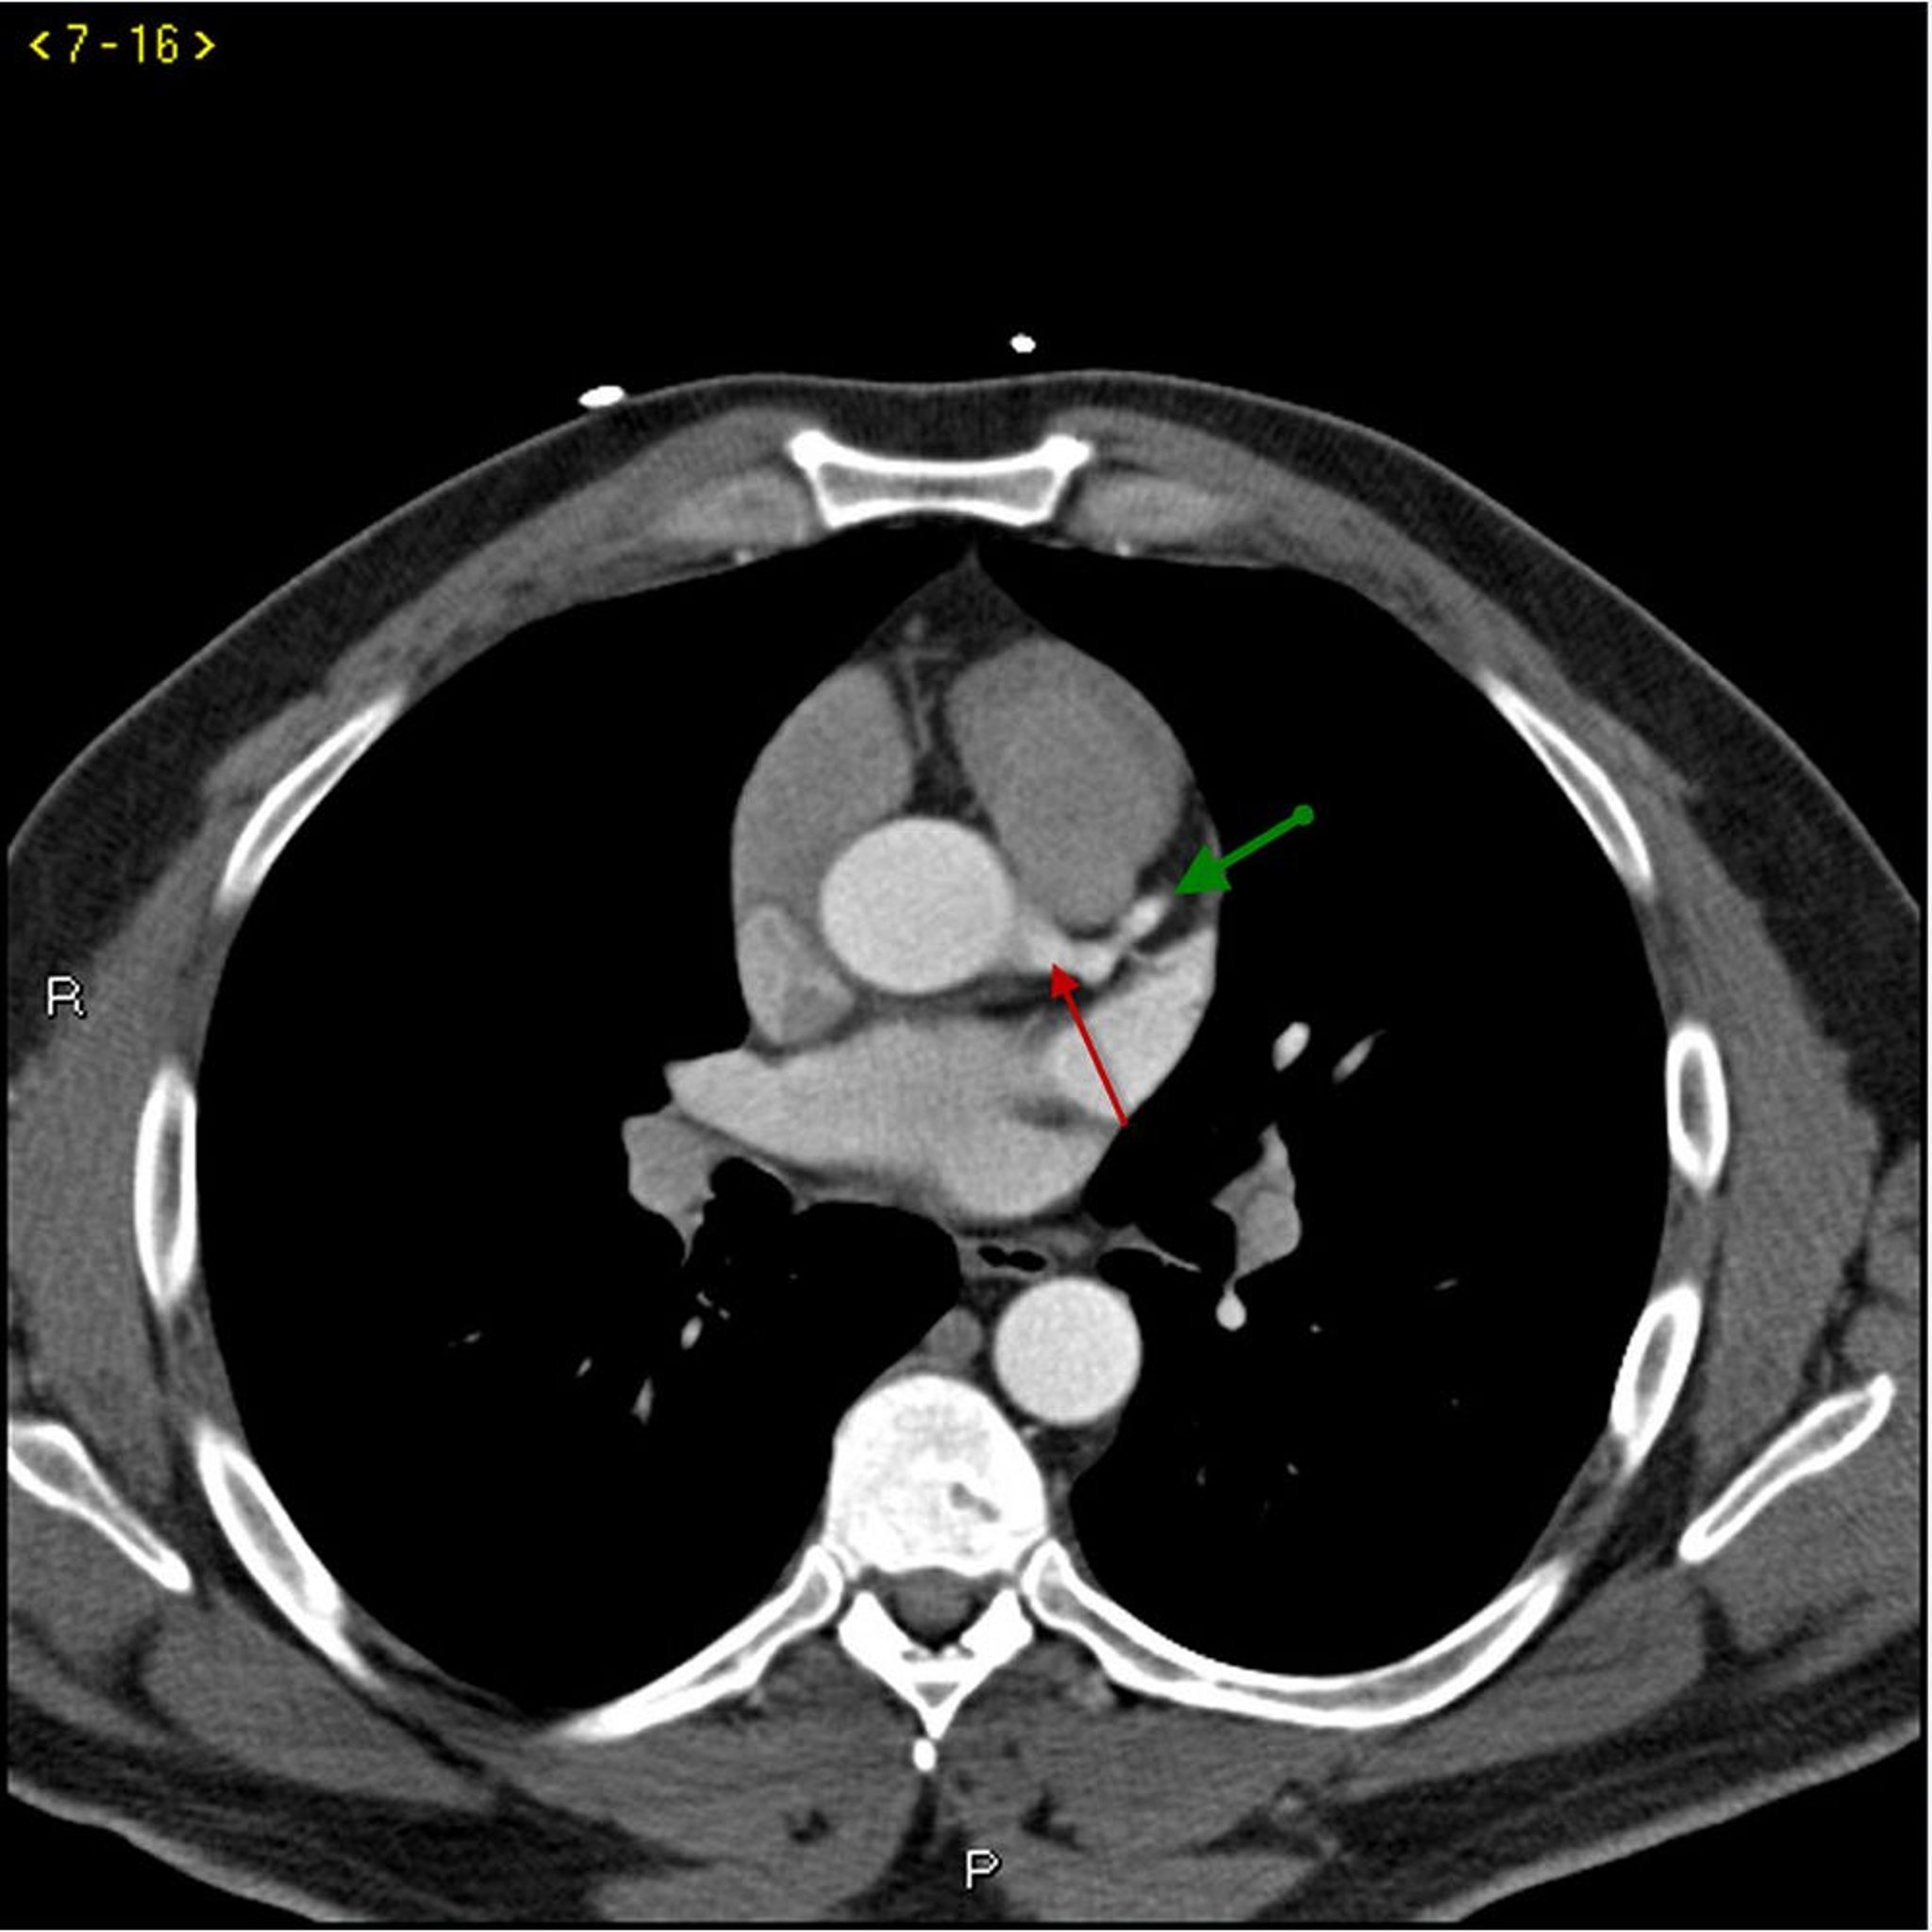

Kontrast CT zeigt normale Koronararterien - Folie 1

Dieses Kontrast-CT zeigt normale Koronararterien. Die linke Hauptleitung ist durch den roten Pfeil gekennzeichnet. Die linke anteriore absteigende Arterie und die linke Zirkumflexarterie sind durch den grünen bzw. blauen Pfeil und die rechte Koronararterie durch den lila Pfeil gekennzeichnet.